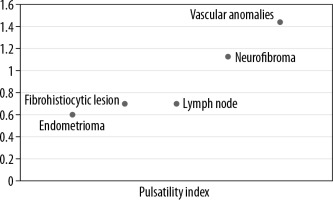

Lipomas, constituting the majority of lesions, were predominantly hyperechoic on conventional ultrasonography, and rest of the lesions were majorly heteroechoic. Doppler assessment was performed to look for the pattern of vascularity and further characteristic parameters, including resistive and pulsatility indices (Figures 1 and 2).

An integrated approach using various ultrasound techniques (greyscale, colour Doppler, and elastography) were performed simultaneously in each case. Conventional ultrasonography was performed following standardised protocols using linear array transducers of frequency 5-17 MHz and 3-9 MHz, and the parameters recorded were location, number, size, shape, echogenicity, and margins for each superficial lesion. Doppler assessment was also done to evaluate the presence or absence of vascularity, pattern of vascularity – whether peripheral or central, and the Doppler parameters (resistivity index, pulsatility index) of the lesions.